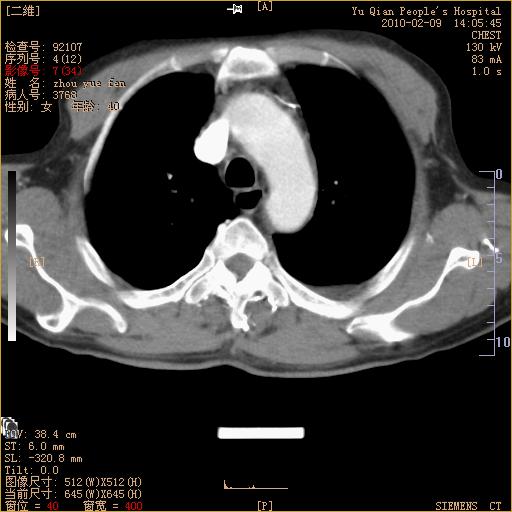

男性,73岁,咳嗽咳血数天,诊为肺ca伴左肺下叶后段阻塞性炎症、肺不张妥否?

左下肺中央型肺癌伴结段形肺不张,左侧胸腔积液,纵隔内见部分增大淋巴结(反应性增生或转移)

左下基底干支气管明显变窄。

左肺下叶基底段支气管狭窄,左肺门增大,左肺下叶团片状病灶。中心型肺癌伴柱塞性炎症可能大,建议支气管镜检查。

左下肺中央型肺癌伴节段性肺不张,左侧胸腔积液,纵隔内见肿大淋巴结

左下基底段支气管变窄。建议进一步纤支镜检查。

1、左肺下叶后基地段肺癌伴阻塞性炎症,左下肺门淋巴结转移。2、左侧胸腔积液。